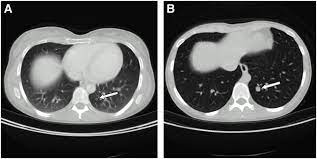

I freaking out today though because i have a hard area in my left breast. Ct scan (computerized tomography) of the chest, abdomen, and pelvis; Cat detects owner's breast cancer before doctors, saving her life call it a sixth sense, a special connection, or just plain mystery. Ct scans can detect bone and joint problems, like complex bone fractures and tumors. A pet/ct scan is a newer technology used to create images of the body's cells as they work. A pet scan will help detect cancer and show how far it has spread. Ct scans can show a tumor's shape, size, and location. Doctors often use ct scans to help them guide a needle to remove a small piece of tissue. After spending a day at the sydney breast clinic, her worst fears were confirmed. A ct scan can be wrong: With cancer cells, they appear as bright spots due to its higher metabolic rate compared to normal cells. For breast cancer, these can include computed tomography (ct or cat) scans and positron emission tomography (pet) scans, this technology offers advanced motion management capabilities and may detect lesions as small as 2.8 millimeters, as well as bone scans to find out if the cancer has spread to the bone, identifying abnormal activity and the. The answer is yes, and american health imaging can help.

A pet scan will help detect cancer and show how far it has spread. Ct scans can produce false negatives and false positives. In some instances, cancers may not show on the scan. Ultrasound may also be used to locate the position of a tumor in order to guide the doctor during a biopsy or aspiration procedure. After spending a day at the sydney breast clinic, her worst fears were confirmed.

Right now, ct scans aren't routinely used to look for breast cancer, but may be used to look at chest, spine, or abdominal problems, such as a herniated disc or. These scans expose you to more. Cat detects owner's breast cancer before doctors, saving her life call it a sixth sense, a special connection, or just plain mystery. In some instances, cancers may not show on the scan. Do ct scans detect breast cancer?